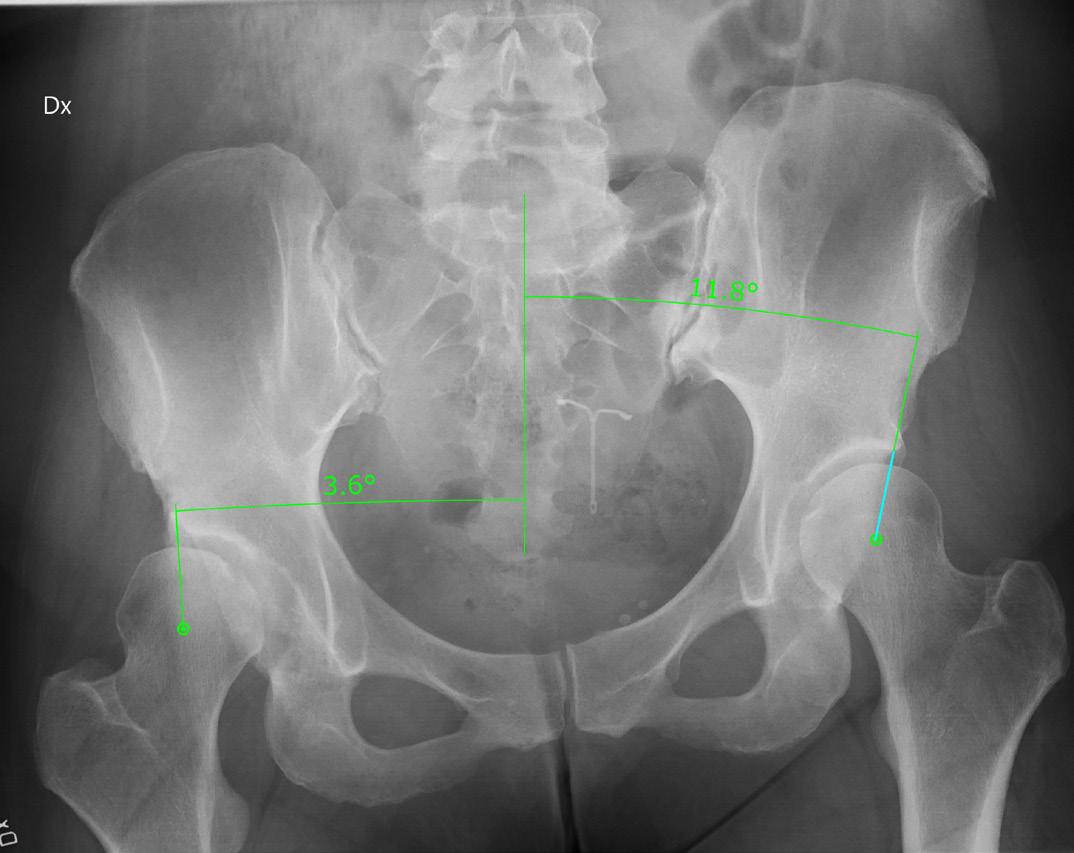

PostPEVA omfattar olika problemtyper; underkorrektion, överkorrektion, talusdeformitet, navicularedeformitet och bal ansering av foten. Under korrierade fötter innefattar kombinationer av spetsfot, varus, cavus, adduktus och framfotssupination medan en överkorrigerad fot in nebär olika grader av valgus fot eller gungfot. Plattfothet eller valgusfot vid postPEVA kan dock inte hanteras som en ”vanlig” plattfothet.

PostPEVA är en stor utmaning för kirurgen! För att kunna hjäl pa patienterna optimalt måste man förstå i) heterogeniteten och komplexiteten i deformiteterna ii) koppling mellan stelhet, fotdeformitet och röntgenförändringar och iii) vad som är or saken till upplevd smärta och funktionsnedsättning.

”PostPEVA” omfattar vuxna PEVA-behandlade patienter (> 16 år) med besvär från sin behandlade fot med kvarstående defor mitet eller en överkorrektion.